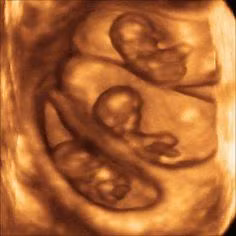

Các bé sinh đôi thường có tư thế nằm trong bụng mẹ không giống nhau. Quá trình quay đầu để chuẩn bị "chui ra" có thể diễn ra ở một hoặc hai bé hoặc thậm chí không diễn ra.

Trong những trường hợp thai nhi không chịu quay đầu để chào đời, các bác sĩ thường chỉ định mổ đẻ để đảm bào an toàn cho mẹ và bé.

Những bé con sinh đôi nằm trong bụng mẹ với rất nhiều tư thế... buồn cười.